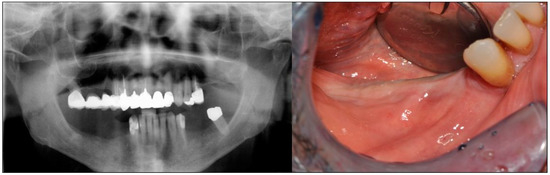

2. Case Description